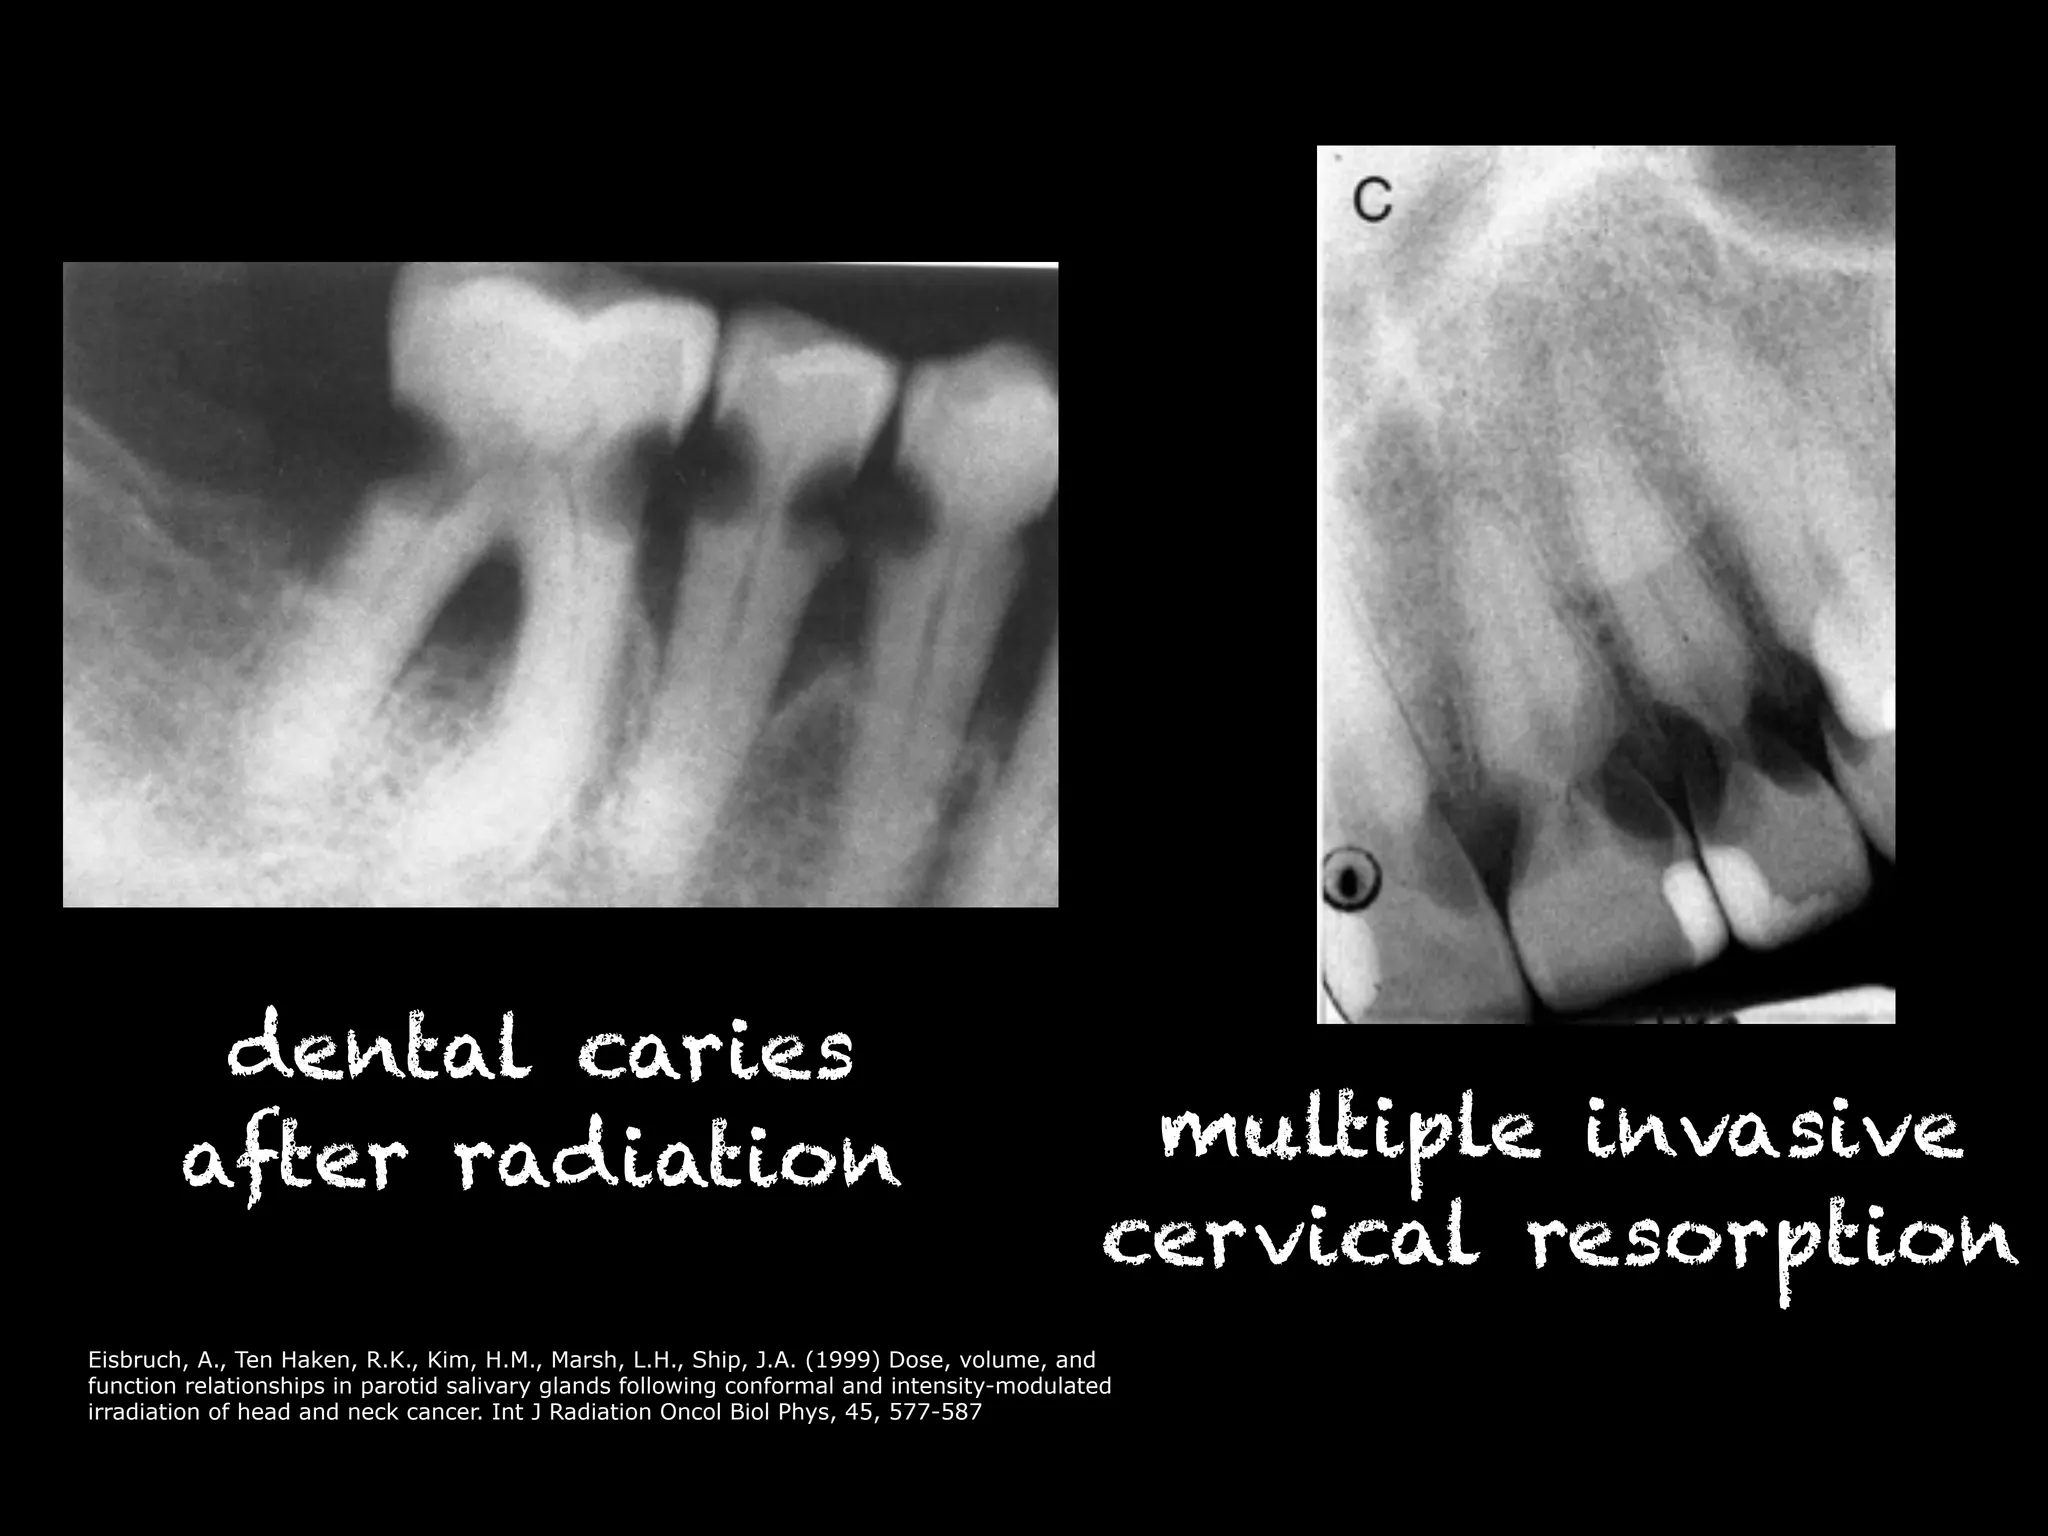

dental caries

after radiation multiple invasive

cervical resorption

Differential diagnosis dentalcaries root resorption

dental caries afterradiation multiple invasive cervical resorption Eisbruch, A., Ten Haken, R.K., Kim, H.M., Marsh, L.H., Ship, J.A. (1999) Dose, volume, and function relationships in parotid salivary glands following conformal and intensity-modulated irradiation of head and neck cancer. Int J Radiation Oncol Biol Phys, 45, 577-587